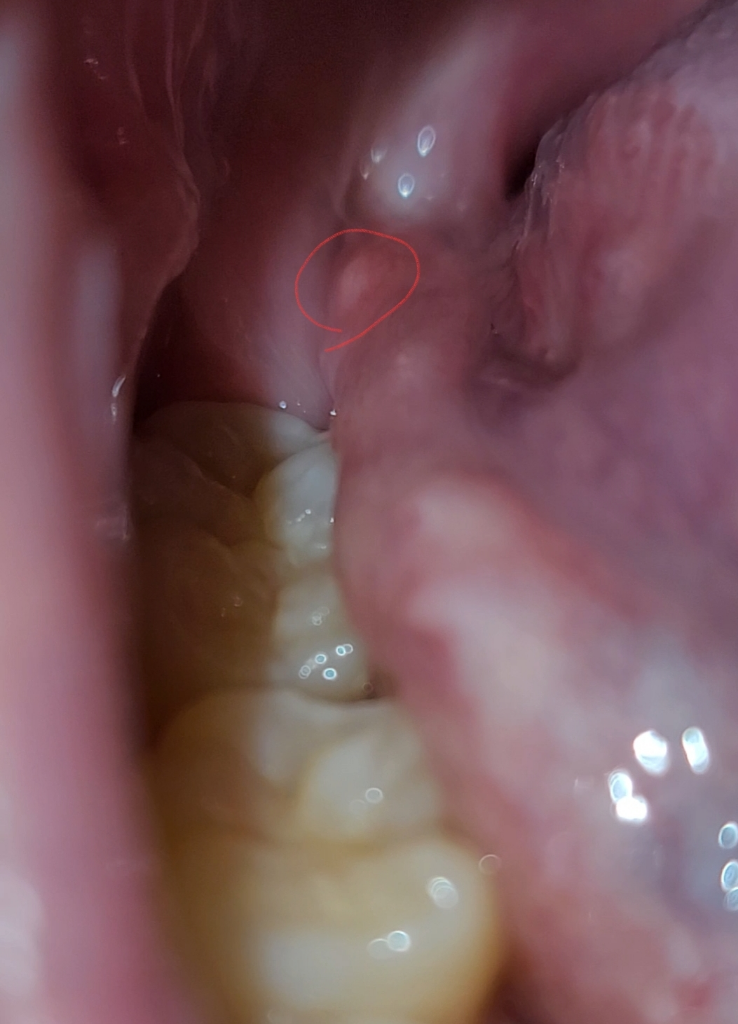

구강에 하얀것이 2주넘게안없어지는데 구강암일까요??

1.빨간색부분이 2주넘게 안없어지네요ㅠㅠ 아프타치도 붙여보고 알보칠도발라봤는데 안없어지네요ㅠㅠ

동네병원 3곳 가봤는데 두곳은 정상구조물이라고하고 한곳은 헐은거라고하던데 말이 달라서요ㅜㅜ

파란색부분은 혈관이 보이는거고 튀어나온건 자극을 받아서 잇몸이 튀어나온것같습니다. 크게 걱정은 안하셔도 될것같습니다.

구강암일 가능성은 낮으며, 피로및 스트레스로인한 구내염일 가능성이 높습니다. 충분한 휴식과 비타민섭취를 하면서 1달정도 지켜보길 권하며, 통증 및 붓기가 없는 경우에는 문제가 되지 않습니다.